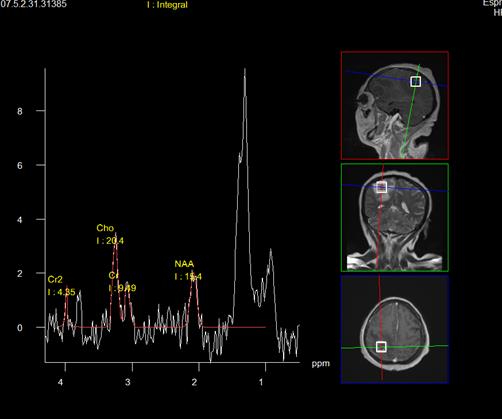

Las pruebas diagnósticas basadas en la imagen son la base para el diagnóstico de la toxoplasmosis cerebral, en la tomografía axial computarizada (TC), se encontraran lesiones hipodensas con forma de anillo por la captación de contraste o únicamente nodulaciones con edema perilesional, y la resonancia magnética (RM), por ser más sensible, permitirá observar lesiones que en la TAC no se lograron detectar; en la tomografía contrastada con fase tardía a los 10 min en la cual es donde las lesiones por toxoplasma muestran su mayor reforzamiento anular. En la espectroscopia se podrá observar un foco inflamatorio con disminución o ausencia de N-acetil aspartato (NAA), un pequeño aumento de colina (Ch) y un pico de lípidos y lactato. También serán útiles, para evaluar el proceso del tratamiento (17,18).

La resonancia magnética nuclear (RMN) de cráneo en secuencias T2 y FLAIR, muestra múltiples imágenes hiperintensas con centro hipointenso, las cuales tienen reforzamiento anular al medio de contraste (realce de anillo) con edema perilesional, distribuidas de manera difusa en ambos hemisferios cerebrales , las de mayor tamaño en lóbulos frontal y parietal derecho, así como en ambos hemisferios cerebelosos, (figuras 2-4). La RMN incluyó espectroscopia donde se aprecia depleción de los niveles de N- acetil aspartato así como aplanamiento de colina y un pico de lípidos (figura 5). Hasta ese momento, no se contaban con otros antecedentes relevantes; sin embargo, ante el cuadro clínico y hallazgos radiológicos se solicita serología para VIH y toxoplasma.

Figura 5. Espectroscopia con aplanamiento en el nivel de Naa, Cho, y pico de lípidos. Cambios los cuales descartan proceso neoformativo.

La biopsia es el estándar de oro para realizar el diagnóstico de esta infección oportunista, pero debido a que las lesiones se encuentran muy profundas y de difícil acceso, se opta por utilizar pruebas diagnósticas basadas en técnicas de neuroimagen, las más empleadas son la TAC y la RM. En la TAC se podrán observar lesiones únicas o múltiples de aspecto hipodenso, habitualmente con edema de gran intensidad, que pueden condicionar efecto de masa, que al administrar el medio de contraste, muestran un patrón de anillo que rodea la lesión (17,18), presentándose en 80-90% de los pacientes con toxoplasmosis cerebral (20). Estos no son datos patognomónicos de la neuroinfección por Toxoplasma gondii, ya que entre los diagnósticos diferenciales que muestran el patrón de anillo por el contraste se enlistan los linfomas primarios del SNC, el glioblastoma multiforme, las metástasis cerebrales, abscesos cerebrales, infartos cerebrales, entre otras (17,18). Además es útil para el diagnóstico diferencial la RMN con espectroscopia donde se describe un patrón inflamatorio habitual, que consiste en un aplanamiento en el nivel de captación de N acetil aspartato (NAA), un pequeño aumento de colina (Ch) y un pico de lípidos y lactato.